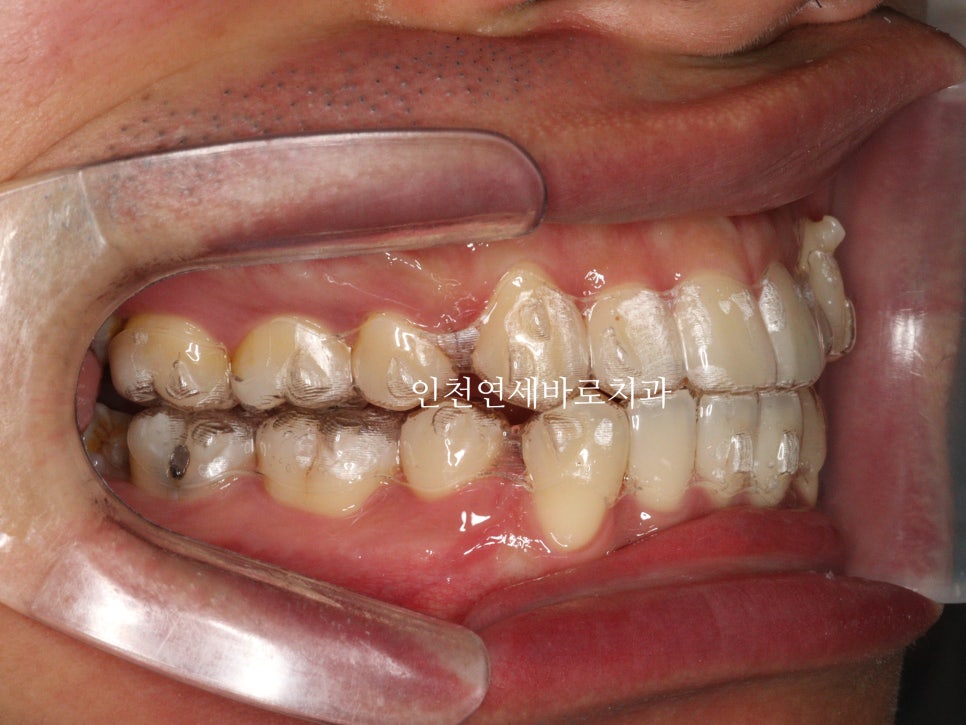

약 1년 4개월이 지난 모습입니다.

첫번째 세트가 마무리 되었고, 원래의 계획이라면 마무리도 가능한 시점입니다.

하지만 중심선과 교합 등 아주 미세한 부분들이 아쉬워 재제작을 권했고, 환자분이 수락해주셨습니다.

재제작 진행.